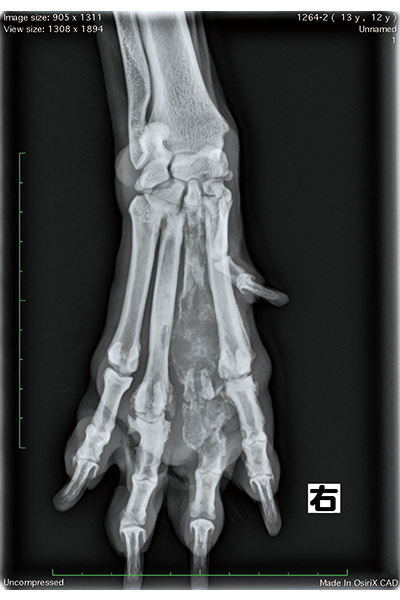

【CASE 1】X線検査にて右前脚第三指に抽出されたマス病変

関根先生 【CASE 1】導入後、最初に検査を行った症例は特に印象深いですね。代々ゴールデン・レトリーバーを飼われているご家族さまの11歳の子に、がん検診としてNu.Q® Vet Cancer Testを行ったところ、グレーゾーン(71 ng/mL)という結果が出ました。そのため、2週間後の再検査を予定していたのですが、1週間で「指が腫れている」と来院されたので、X線検査を行うと骨肉腫が疑われました。CTを撮影し画像を読影した結果、骨盤や脊椎にも転移が見られ進行した骨肉腫と診断しました。この子は、指の腫れはあったものの、痛みがなく、跛行も見られなかったので、Nu.Q® Vet Cancer Testを測定していなければ骨肉腫だと分からなかった可能性が高いと思います。また、グレーゾーンという結果が出たことで、ゴールデン・レトリーバーのことをよく理解されているご家族さまがいつも以上に注意して観察されていたからこそ、指の腫れに気づけたのではないかと思います。